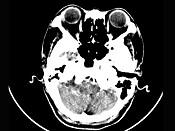

问题 女,45岁,右耳听力下降半年余,CT检查如图,最可能诊断为()

选项 A.继发性胆脂瘤 B.脑膜瘤 C.三叉神经瘤 D.原发性胆脂瘤 E.听神经瘤

答案 E